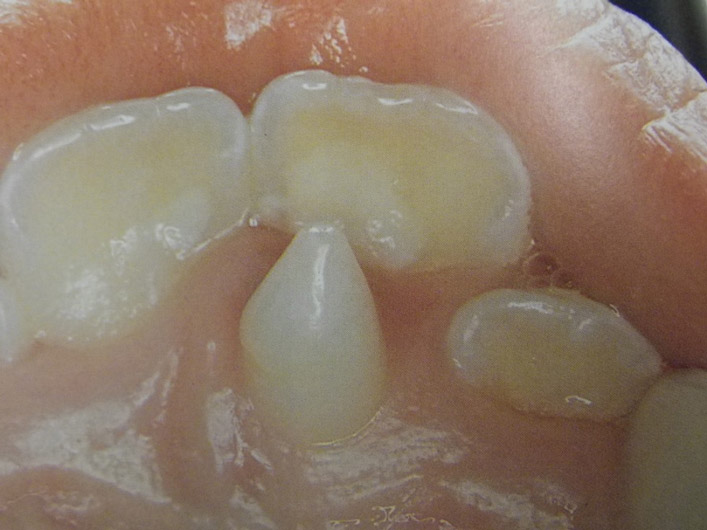

Τερηδόνα βρεφικής και νηπιακής ηλικίας ή τερηδόνα θηλασμού

Η τερηδόνα βρεφικής και νηπιακής ηλικίας εμφανίζεται σε μικρά παιδιά ηλικίας 2 έως 5 ετών, τα οποία έχουν τερηδονισμένα ένα ή και περισσότερα νεογιλά δόντια. Η τερηδόνα αυτής της μορφής οφείλεται σε λάθος τρόπο διατροφής του παιδιού και μπορεί να εξελιχθεί γρήγορα και σε μεγάλη έκταση επηρεάζοντας το σύνολο το δοντιών που βρίσκονται στο στόμα.

Η κυριότερη αιτία εμφάνισης της τερηδόνας αυτής της μορφής είναι το τάισμα με το μπιμπερό ενώ το παιδί κοιμάται. Κατά τη διάρκεια του ύπνου η ποσότητα του σάλιου μειώνεται και το γάλα, ανεξάρτητα αν περιέχει ή όχι ζάχαρη, παραμένει πάνω στα δόντια και προκαλεί τερηδόνα. Ακόμη και το μητρικό γάλα μπορεί να έχει τις ίδιες συνέπειες, εφόσον το παιδί θηλάζει κατά βούληση κατά τη διάρκεια της νύχτας.